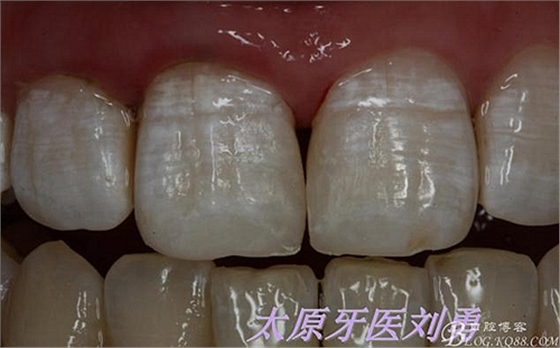

術(shù)后即刻如下圖:

術(shù)后5小時(shí)復(fù)查如下圖: